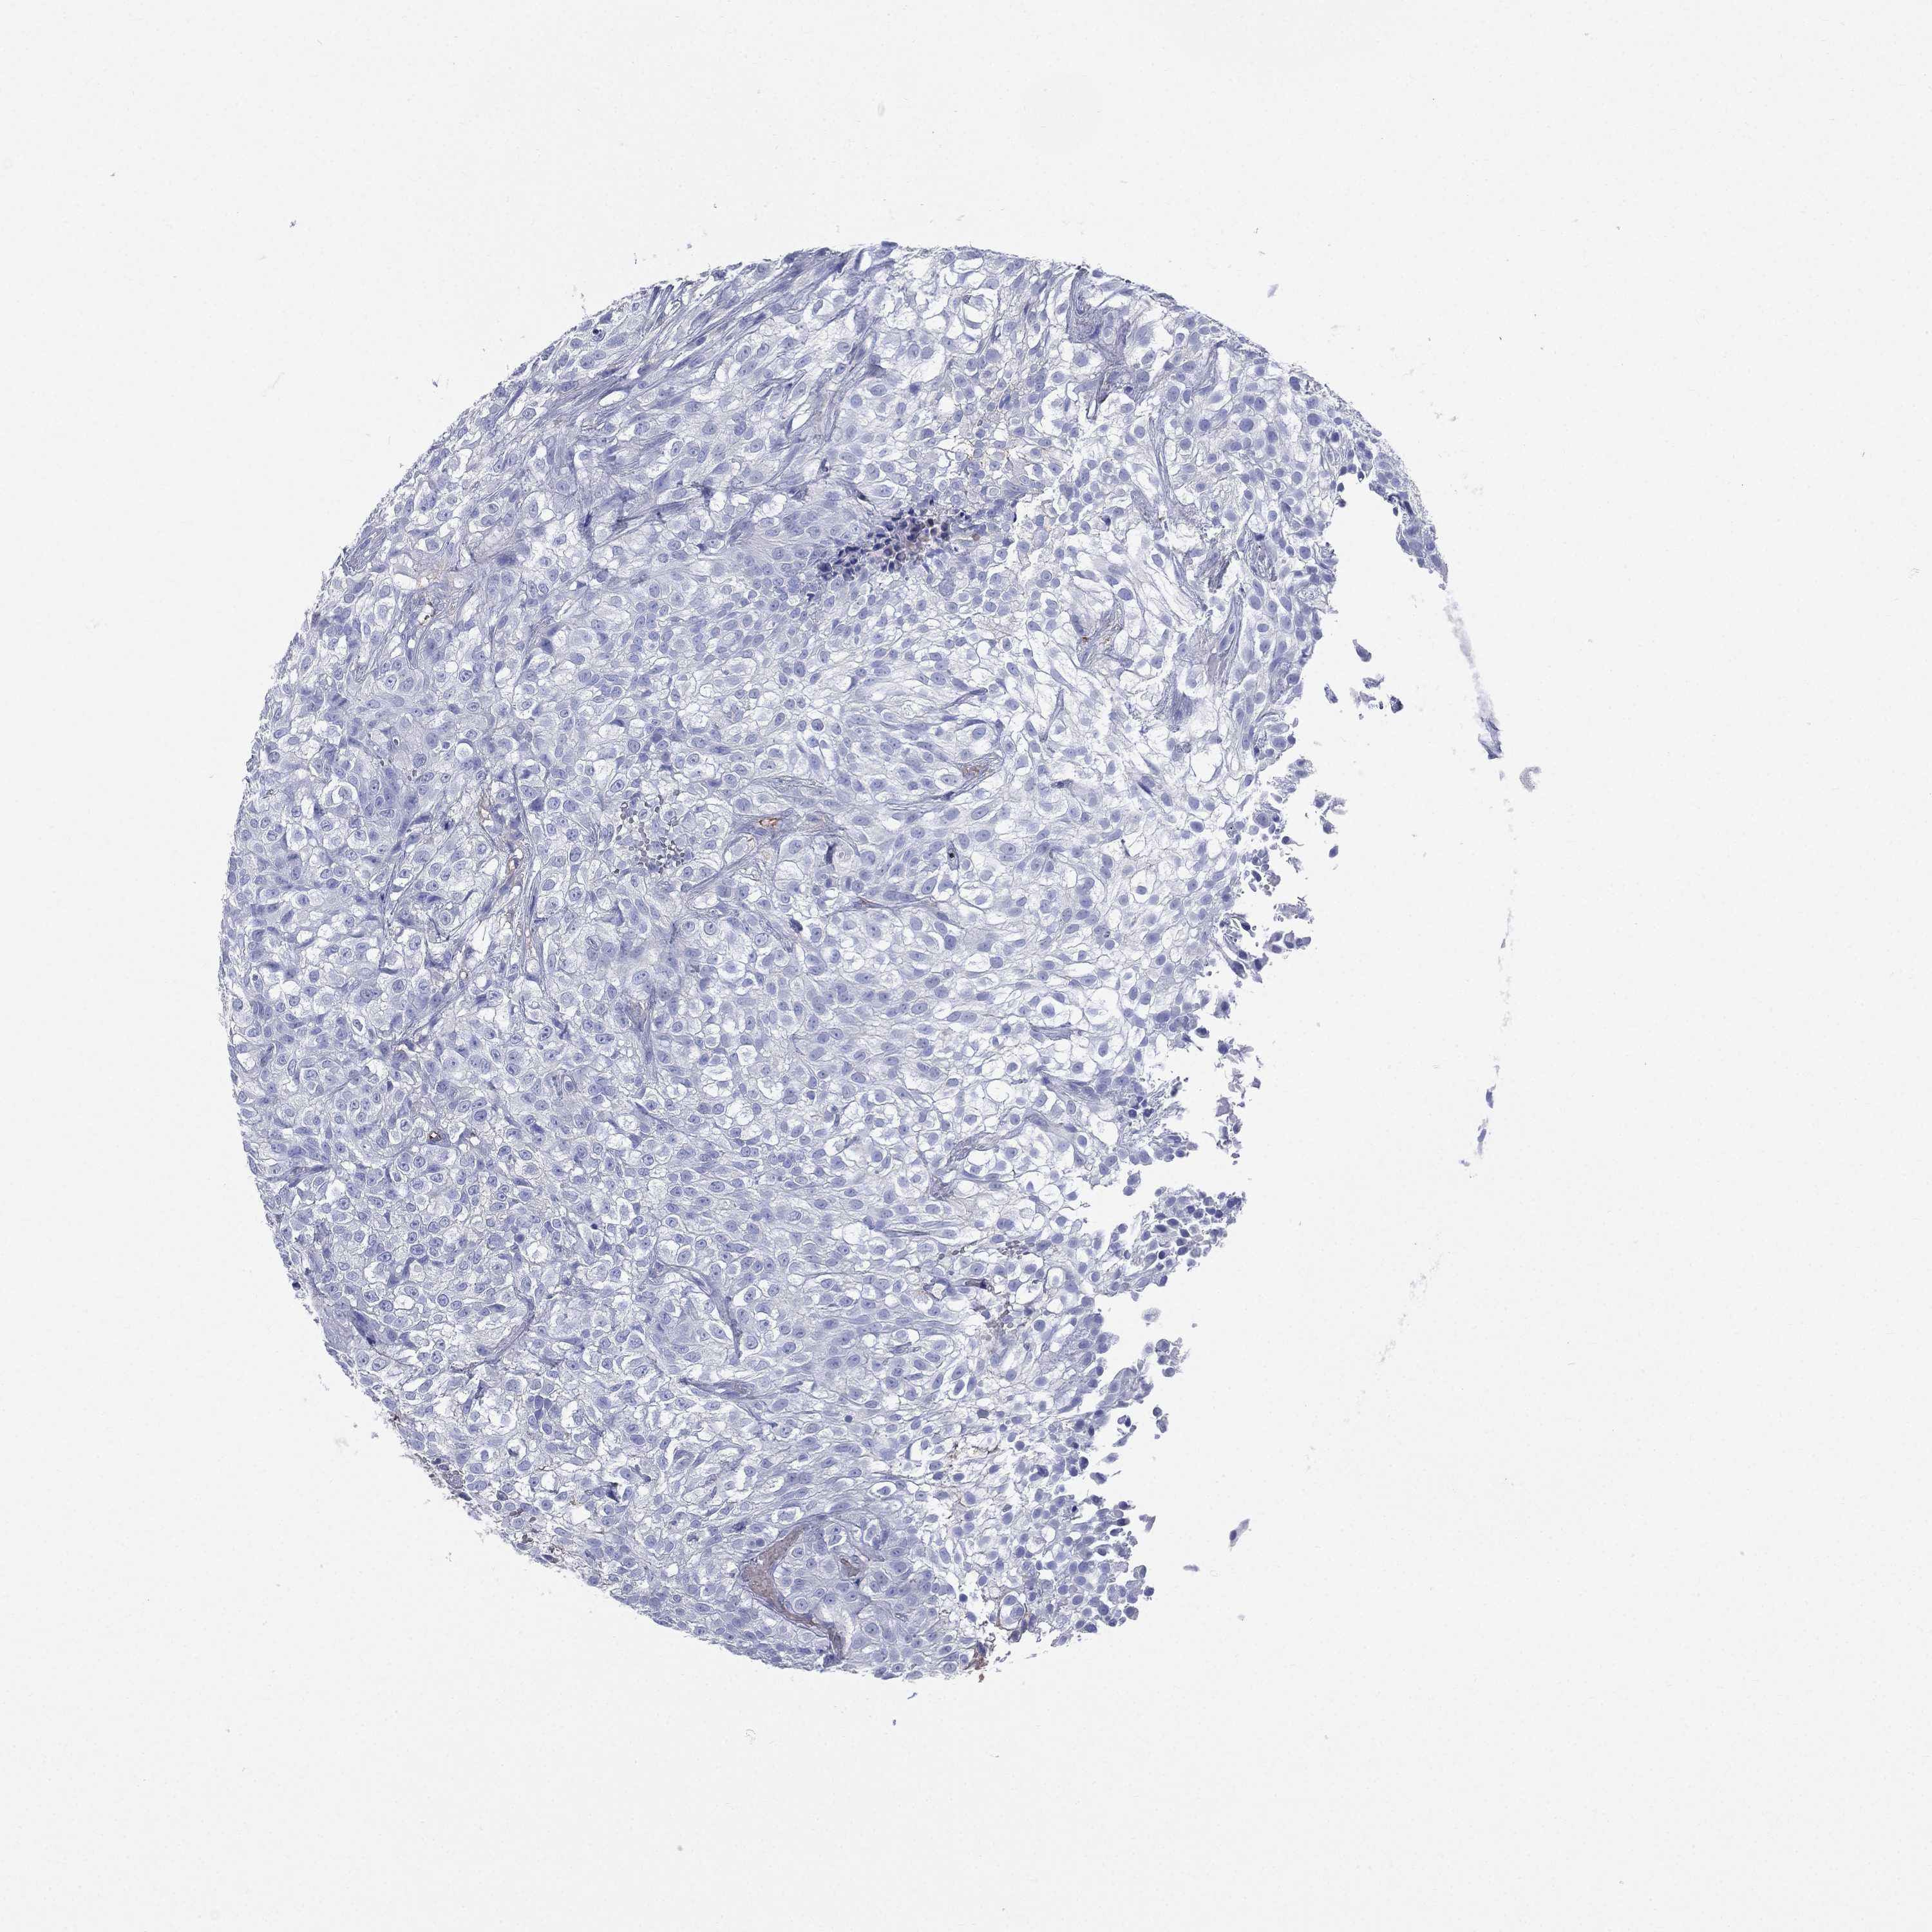

UROTHELIAL CANCER - Protein expressioni

A mouse-over function shows sample information and annotation data. Click on an image to view it in a full screen mode. Samples can be filtered based on level of antibody staining by selecting one or several of the following categories: high, medium, low and not detected. The assay and annotation is described here.

Note that samples used for immunohistochemistry by the Human Protein Atlas do not correspond to samples in the TCGA dataset.

Antibody stainingi

Antibody staining in the annotated cell types in the current human tissue is reported as not detected, low, medium, or high, based on conventional immunohistochemistry profiling in selected tissues. This score is based on the combination of the staining intensity and fraction of stained cells.

Each image is clickable and will lead to virtual microscopy that enables deeper exploration of all samples and also displays staining intensity scores, fraction scores and subcellular localization as well as patient and tissue information for each sample.

Antibody HPA047750

Antibody HPA066795

Antibody CAB003787

Urothelial carcinoma, High grade

Urothelial carcinoma, NOS

Urothelial carcinoma, Low grade